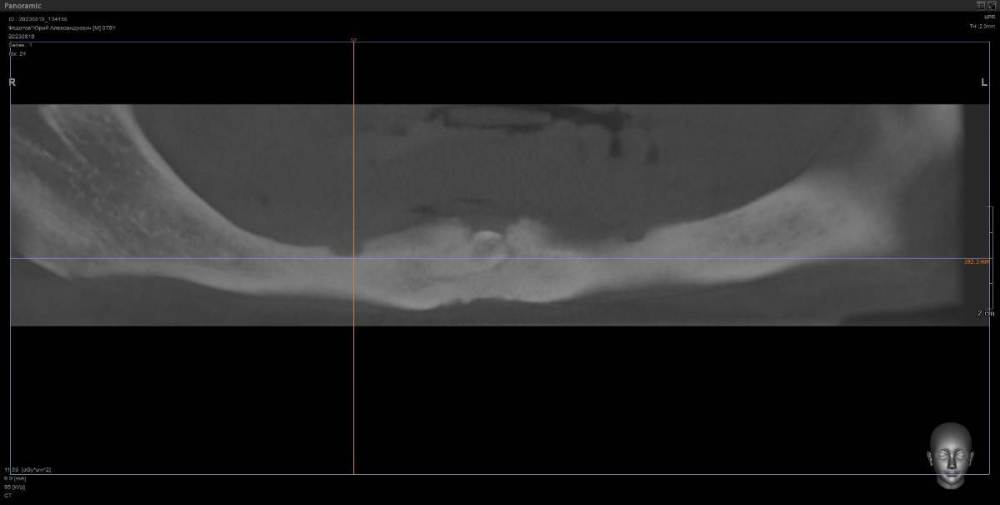

kriokov Опубликовано 10 августа, 2023 Поделиться Опубликовано 10 августа, 2023 ретенция клыка справа. кость 1 тип. Выход нерва почти по вершине. Сьемник не держится. М- 70 лет. Здоров. Нужен совет по установке имплантата справа под локатор, без удаления клыка. Слева штатно. Ссылка на комментарий

annda Опубликовано 13 августа, 2023 Поделиться Опубликовано 13 августа, 2023 (изменено) Предположу, что это должны быть как раз первые 4- 6 мм имплантата , корональная его часть( как при синус лифтинге том же) . в данном кейсе ( на втором соезе, что показан) совсем же другая ситуация. В этом ракурсе можно срез посмотреть не через коронку клыка, а через апикальную треть корня, над которым как раз и лежит массив своей губчатой кости.Посмотреть, сколько его там. А самый первый срез чем не устраивает ?Там область за местом выхода СНП или я не понимаю чего-то? Изменено 13 августа, 2023 пользователем annda Ссылка на комментарий

kriokov Опубликовано 13 августа, 2023 Автор Поделиться Опубликовано 13 августа, 2023 10 часов назад, annda сказал: А самый первый срез чем не устраивает ?Там область за местом выхода СНП или я не понимаю чего-то? Думаю првильно понимаете, это более менее позиция, 6 часов назад, TIGER сказал: 2 импланта под 30 гр м.ю,балочка между ними,и никакого гемора с клыком и локаторами как вариант, да + Ссылка на комментарий